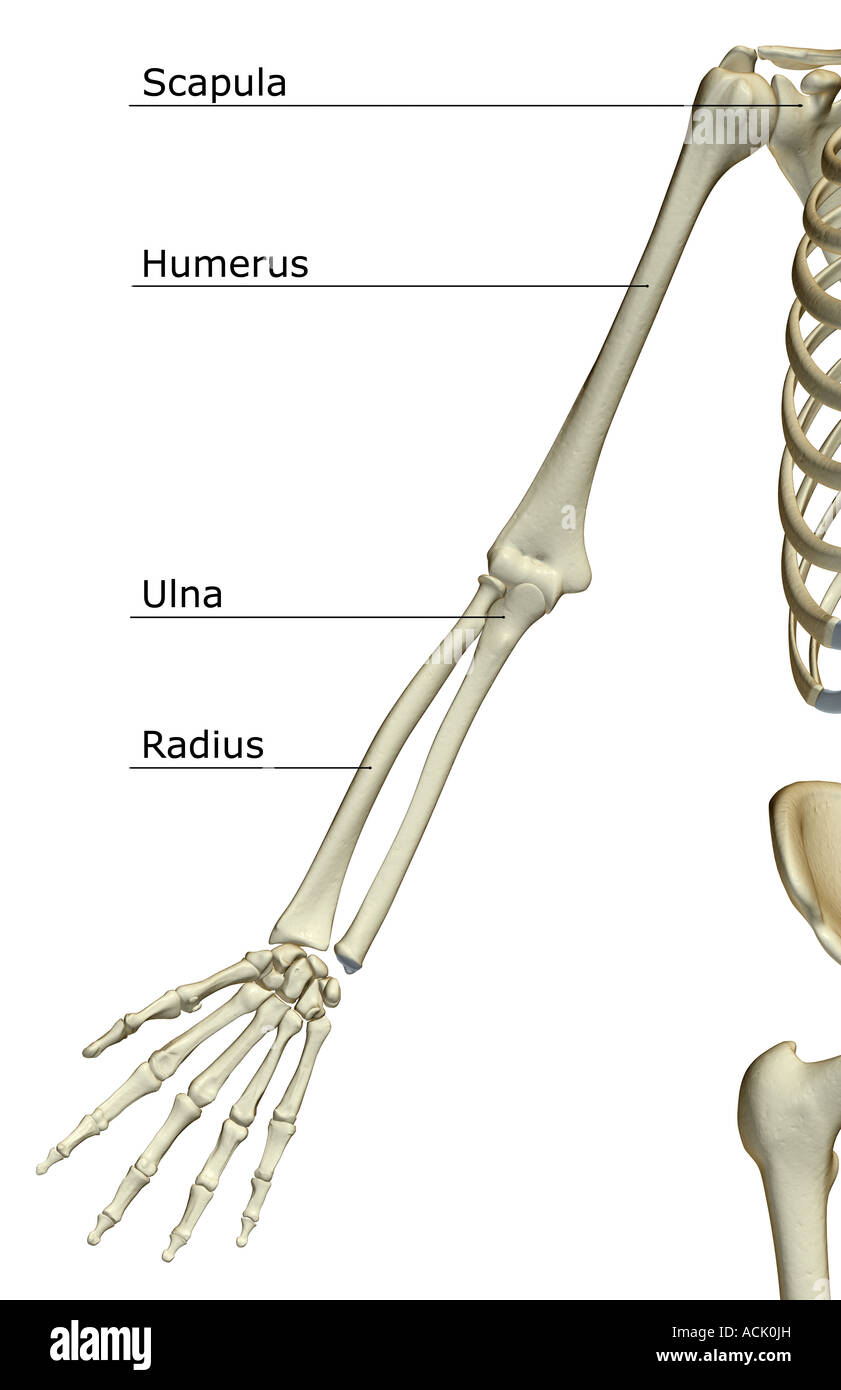

RF2JNYJM7–Präzise Knochen des Arms oder der oberen Extremität des menschlichen Skelettsystems oder Skeletts isoliert auf weißem Hintergrund 3D Rendering Illustration. Anterior und

RF2K1XTCE–Anatomie des menschlichen Arms. Knochen und Gelenke von Arm, Unterarm und Hand. Vorderansicht des oberen Gliedes des Skeletts. Vektorgrafik

RF2JNYJM8–Genaue vordere oder vordere Ansicht der Knochen des Arms oder der oberen Extremitäten des menschlichen Skelettsystems isoliert auf weißem Hintergrund 3D Rendering Illustration. Ein